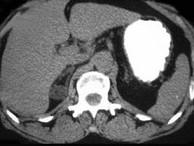

问题 女,35岁,无意中发现血压高,实验室检查:血和尿中醛固酮水平增高,请结合所提供图像,作出诊断 ( )

选项 A、右肾上腺转移瘤 B、右肾上腺囊肿 C、右肾上腺Cushing腺瘤 D、右肾上腺皮质腺瘤 E、右肾上腺增生

答案 D